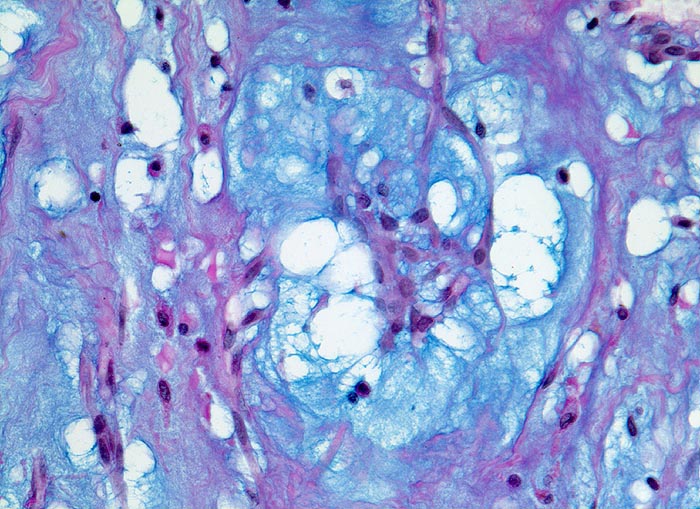

AP/ Vorhofmyxom

Vorhofmyxom